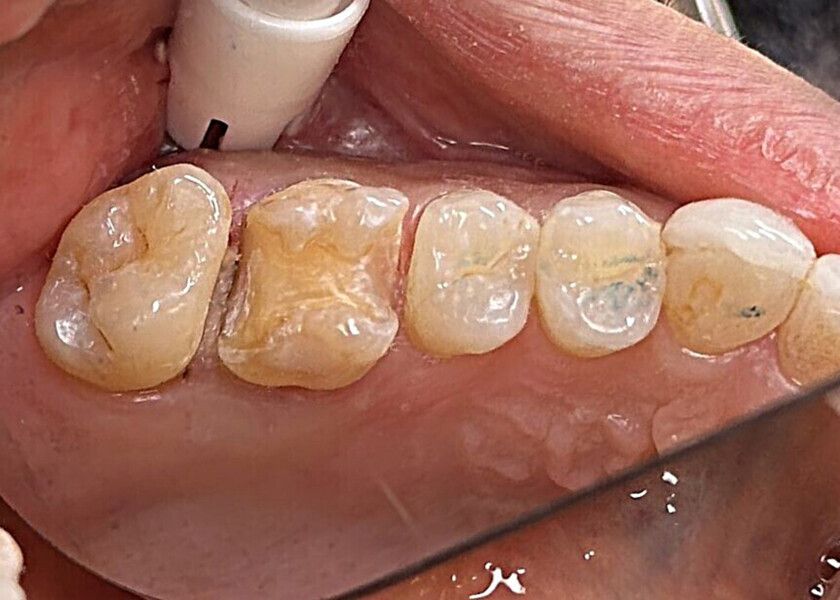

Fig. 19: Clinical view of the old composite restorations with recurrent caries on the molars and premolars.

A 23-year-old female patient presented with cold sensitivity of the teeth in the maxillary right posterior sextant. Examination noted old composite fillings in the molars and premolars and recurrent caries on each tooth (Fig. 19). A bitewing radiograph was taken to evaluate the extent of the recurrent caries and the dimensions of the composite restorations (Fig. 20). Owing to the dimensions of the restorations and caries, inlay and onlay restorations were suggested to restore the teeth and preserve tooth structure as an alternative to complete crowns. The patient’s questions were answered, and she agreed to the proposed treatment. She was informed that the treatment could be completed in a single appointment utilising 3D printing for restoration fabrication. Time in the schedule permitted treatment to be performed during that same appointment. Our intent is to provide conservative restoration with superior accuracy and definition compared with milling, as well as better predictability and mechanical properties compared with direct resin composite restorations.